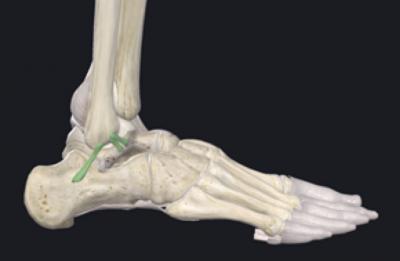

L’entorse de cheville est le traumatisme le plus fréquent en traumatologie, avec environ 6500 cas par jour en France. Elle correspond à une lésion ligamentaire, le plus souvent sur un mécanisme de varus équin. Selon la gravité : étirement (bénigne), rupture partielle (moyenne) ou rupture complète (grave).

Les entorses concernent principalement le ligament collatéral latéral, mais peuvent aussi impliquer le médial, la syndesmose tibio-fibulaire, ou les articulations du médio- et avant-pied (Chopart, Lisfranc).

Défini par une sensation d’insécurité ou d’instabilité avec antécédents d’entorses répétées. Les facteurs favorisants incluent varus de l’arrière-pied, déficit de flexion dorsale par rétraction du triceps sural. L’examen recherche une laxité clinique (testing varus, tiroir antérieur) et radiologique (varus forcé ≥10°, tiroir ≥8 mm). L’IRM ou l’échographie complètent le bilan morphologique. Dans certains cas l’arthroscanner est necessaire pour les lesions cartilagineuses.

7. Principes de la chirurgie ligamentaire